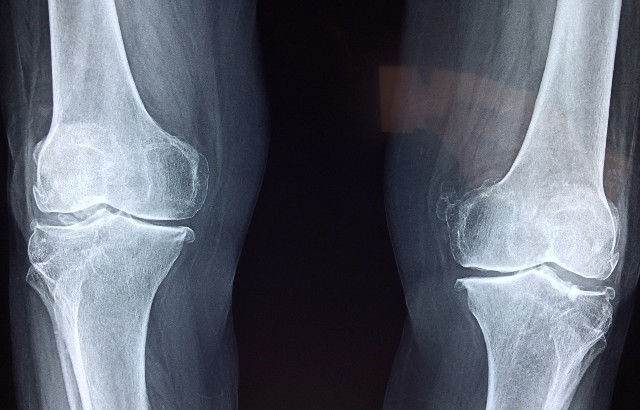

Knee x-ray. Image by Dr. Manuel González Reyesa from pixabay